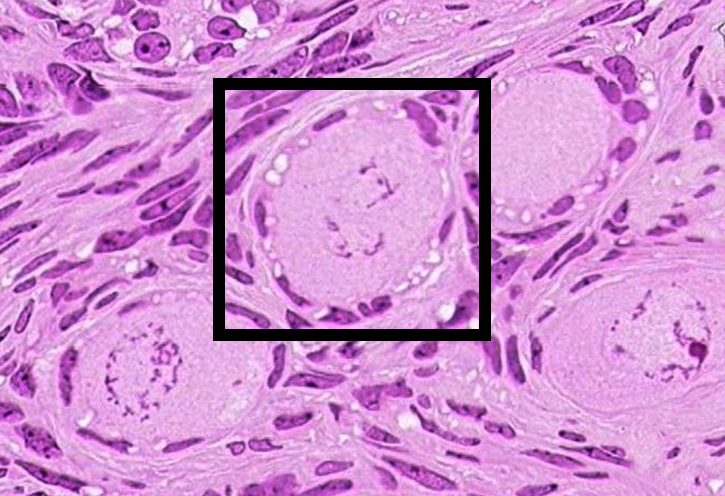

Identify the type of follicle within the black box in the figure below.

A. primordial

B. early primary

C. late primary

D. secondary

E. Graafian

A. primordial

Examine the structure in the boxed region on this: https://www.digitalscope.org/ViewerUI/?SlideId=6adbd7ff-2cf6-4c60-8fb2-b44f9dd7ba98

Why is this structure classified as endocrine tissue?

A. Cells in this nest within the anterior pituitary release hormones that directly inhibit the actions of target organs.

B. Cells within this zone of the adrenal cortex release steroid hormones that migrate to the nucleus of target cells and directly regulate gene expression.

C. Cells lining this follicle in the thyroid produce hormones derived from amino acids.

D. Cells of this pancreatic islet produce hormones that are released directly into the bloodstream.

E. Cells within this region of the neurohyphophysis receive neural input from the hypothalamus, allowing for integration of nervous input and body response

D. Cells of this pancreatic islet produce hormones that are released directly into the bloodstream.